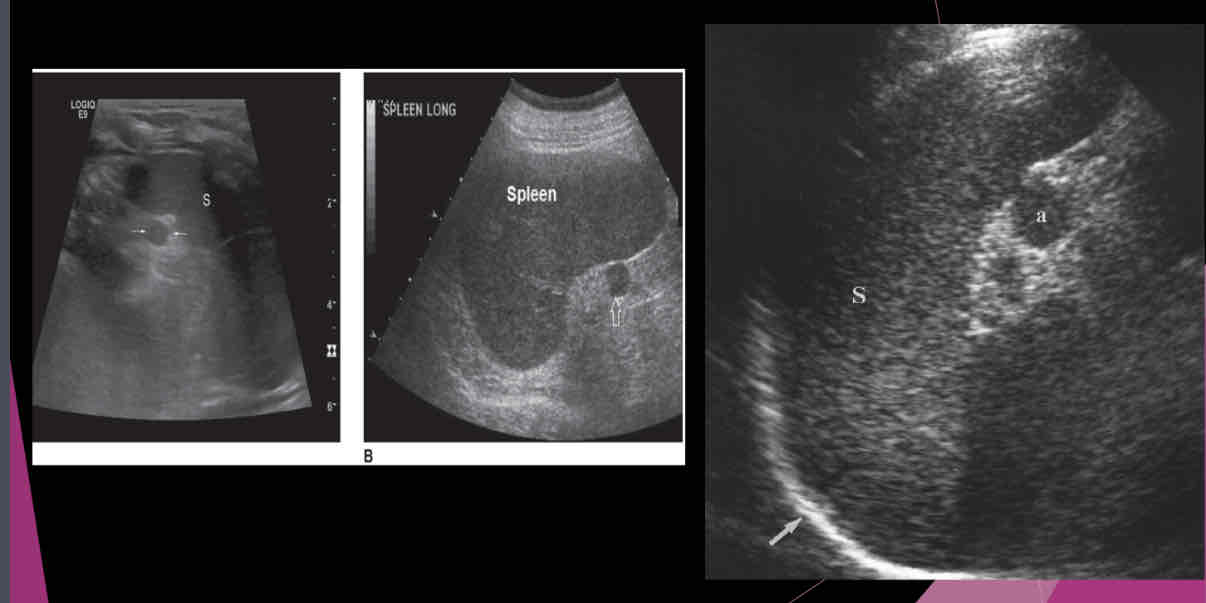

Describe the spleen on US?

-Homogeneous texture

- Echogenicity the same as or slightly below the normal liver echogenicity

- Smooth border at diaphragm

- Intercostal coronal view used to obtain spleen length

- Average length 11-13cm; usually decreases in size with age

- Usually 2/3 size of the liver

- Deep inspiration usually necessary to evaluate the entire organ

What is a relatively common anatomic variant?

accessory spleen (Splenule)

Most accessory spleens are small and measure between…

1.5 and 2.0 cm

An accessory spleen or splenule is _______ to spleen

hypoechoic

Isoechoic

hyperechoic

heterogeneous

Isoechoic